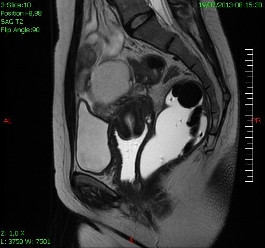

Nodule d’endométriose de la cloison recto-vaginale, vu en IRM.